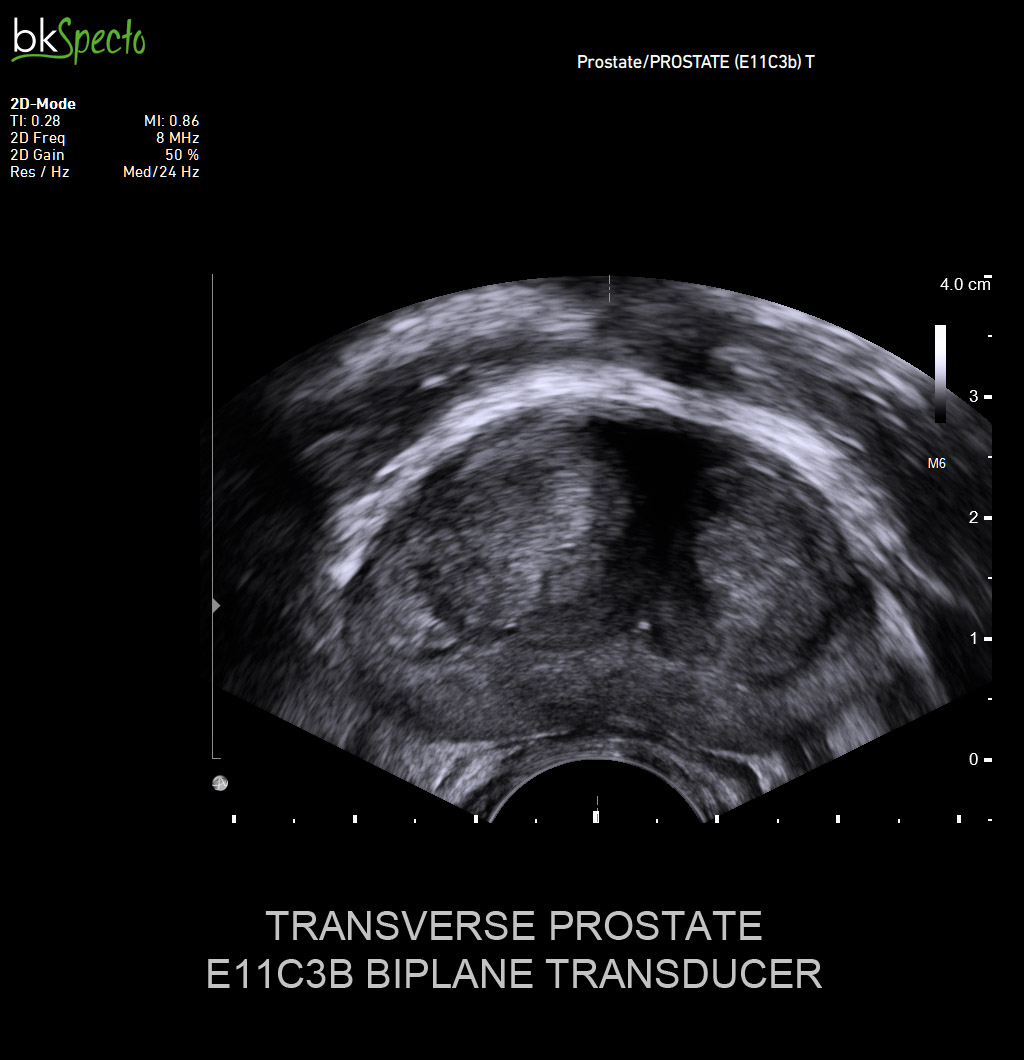

BkSpecto là hệ thống siêu âm chuyên về các thủ thuật can thiệp cho các chuyên khoa: Tiết niệu, gây mê, cơ, tuyến vú, tuyến giáp, sản phụ khoa và hậu môn trực tràng.

- Là thương hiệu đầu tiên và hàng đầu thế giới với hơn 40 năm chuyên về sinh thiết và dẫn hướng điều trị qua hình ảnh siêu âm. BkSpecto được thiết kế đặc biệt cho các ký thuật: Sinh thiết u xơ tiề liệt tuyến, sinh thiết qua đồng bộ hình ảnh siêu âm và MRI, điều trị u bằng đặt hạt phóng xạ, thăm khám dương vật/tinh hoàn, thăm khám thận/bàng quang, tán sỏi thận qua da PCNL.